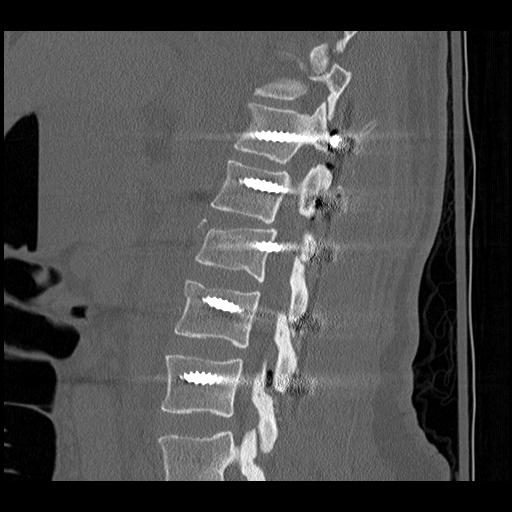

Anterior corpectomy and strut graft

Indication

- decompression of retropulsed fragments in patient with neurology

Technique

- approach as per level

- thoracoabdominal for T11 - L1

- thoracotomy for T2 - T10

- remove disc above and below and remove vertebral body

- remove fragments / need to know if 1 or 2

- screws in vertebral body above and below

- 2 screws in a lateral plane

- insert fibular strut allograft / titanium cage

- augment with cage